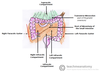

What is this muscle?

Rhomboid major

What is this muscle

The Rhomboid minor